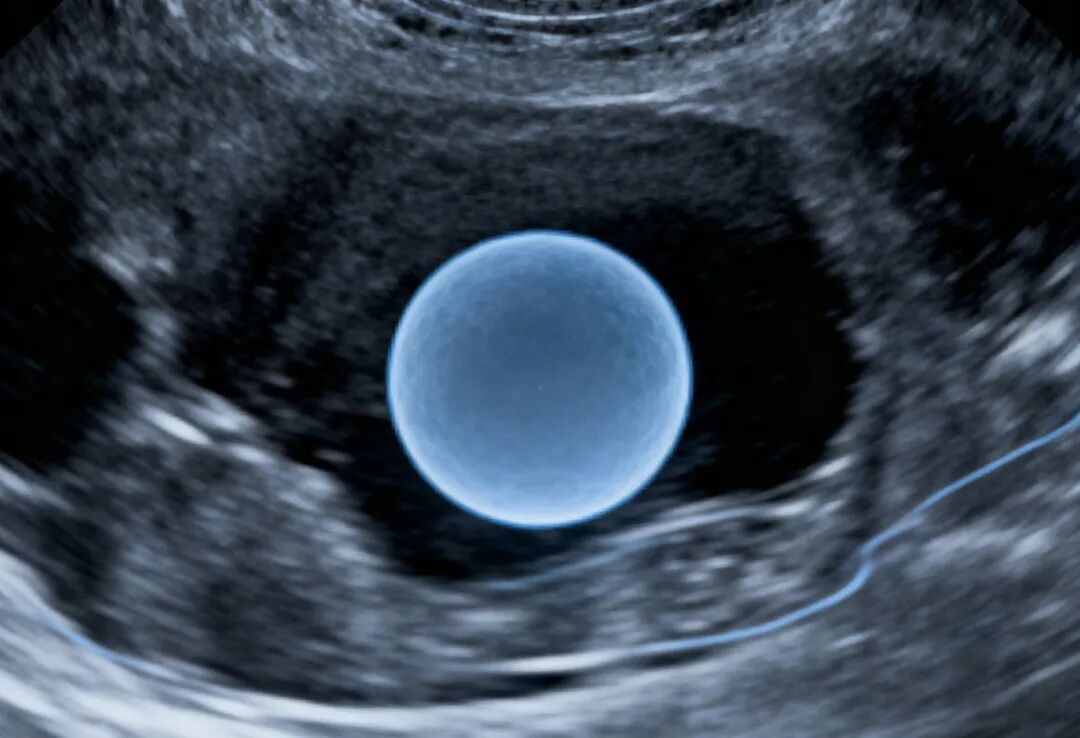

试管移植前养出“好内膜”,是提高胚胎着床率非常关键的一步。一个“好内膜”通常需要满足三个标准:厚度达标、形态良好、血流丰富。